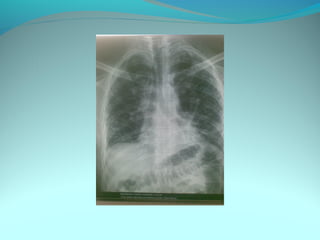

Opacité occupant la partie externe du 1/3 infer du poumon droit

dense et homogene ovalaire de 8cm de grand axe vertical

La limite externe se confend avec une opacité d’environ 1cm comble

les coupole costodiaphragmatique droit

Limitée a sa partie sup par la petit sessure qui est epaisse et pas de

lyse costale

 DIAGNOSTIC :DIAGNOSTIC :

 1_1_cancer bronchique droit( d epaississement)

 2_2_ kyste hydatique au stade sain